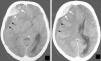

Intracranial extradural hematoma associated to sinusitis and subdural empyema

Hematoma epidural intracraneal asociado con sinusitis y enfisema subdural